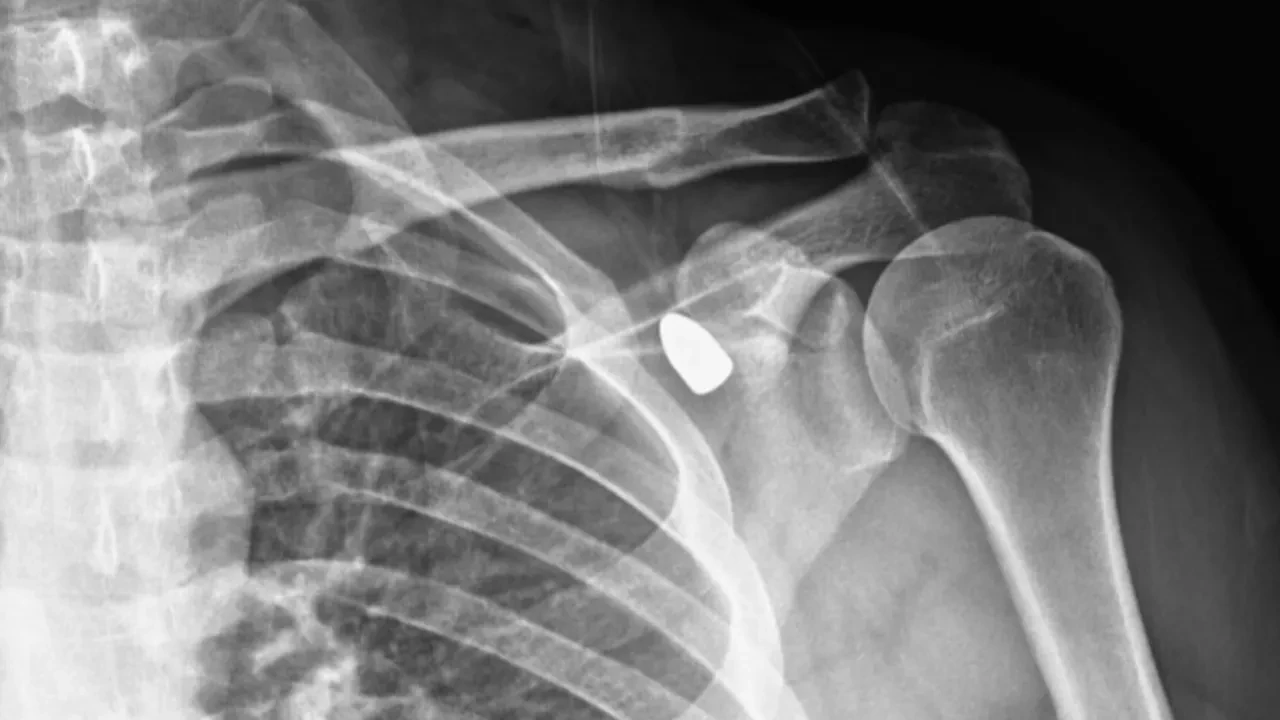

Konya’da yaşayan okul müdürünün koluna 6 yıl önce yorgun mermi saplandı. Ancak merminin bulunduğu yer riskli bölge olduğu için çıkarılaması mümkün olmadı. 6 yılın ardından okul müdürünün omzundaki mermi kendiliğinden yer değiştirince operasyonla çıkarıldı.

Konya’da okul müdürü olarak görev yapan Celal Şenyiğit altı yıl önce çay ocağında otururken omzuna yorgun mermi isabet etti. Yapılan muayeneler sonucunda merminin yerinin hareket kaybı riski taşıdığı tespit edilmesi üzerine herhangi bir operasyon yapılmadı.

6 yıl boyunca omzundaki mermi ile yaşayan okul müdürü ağrı ve sertlik şikayetiyle Akşehir Devlet Hastanesine başvurdu. Yapılan muayenelerde koltuk altındaki kitlenin, omzuna saplanan yorgun mermi olduğu tespit edildi. Mermi, gerçekleştirilen operasyonla çıkarıldı. Okul müdürü Celal Şenyiğit, olayla ilgili şikayetçi olduğunu ve çıkarılan merminin incelemeye gönderildiğini ifade etti.